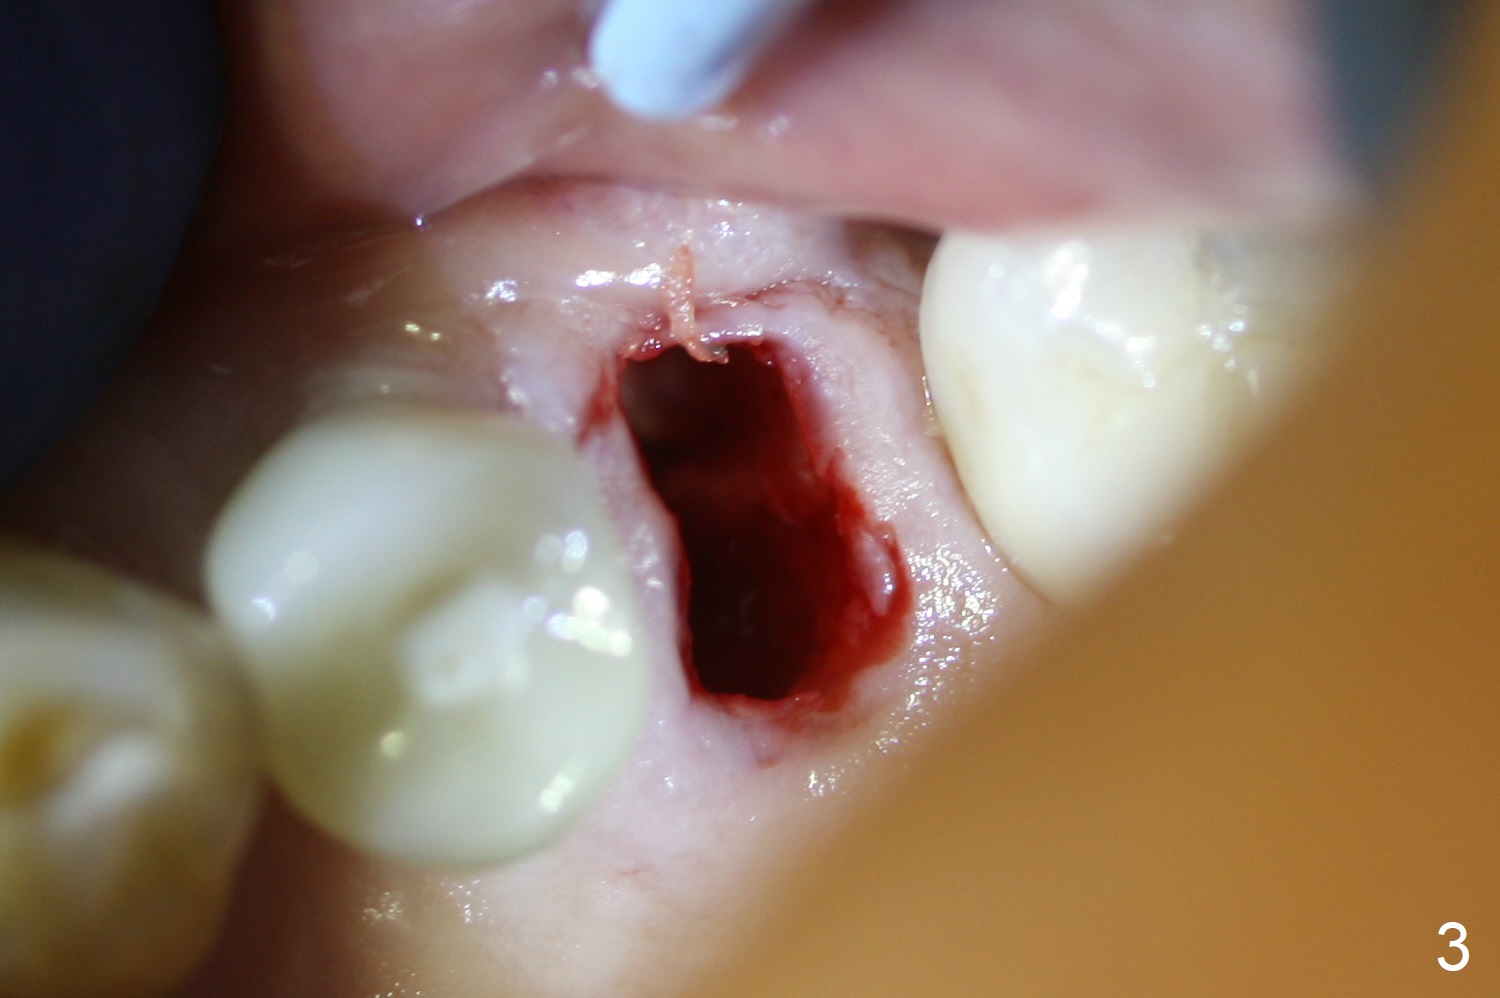

When the tooth #13 with buccal fistula is extracted, the root is found to have vertical fracture (Fig.1). The socket is 14 mm deep (gingival level); the initial osteotomy depth is 20 mm (6 mm to be in the native bone for primary stability, Fig.2). A 4.5x20 mm tissue-level implant (>60 Ncm) is going to be placed in the palatal aspect of the oval socket (Fig.3-5). The localized defect in the buccal plate as indicated by labels (* (Vanilla/Osteogen), B (buccal) and < (perforation) in Fig.6,7 (CBCT coronal and axial sections) is repaired by the bone graft. The bone and gingiva are healthy around the implant nearly 4 months postop (Fig.8,9).